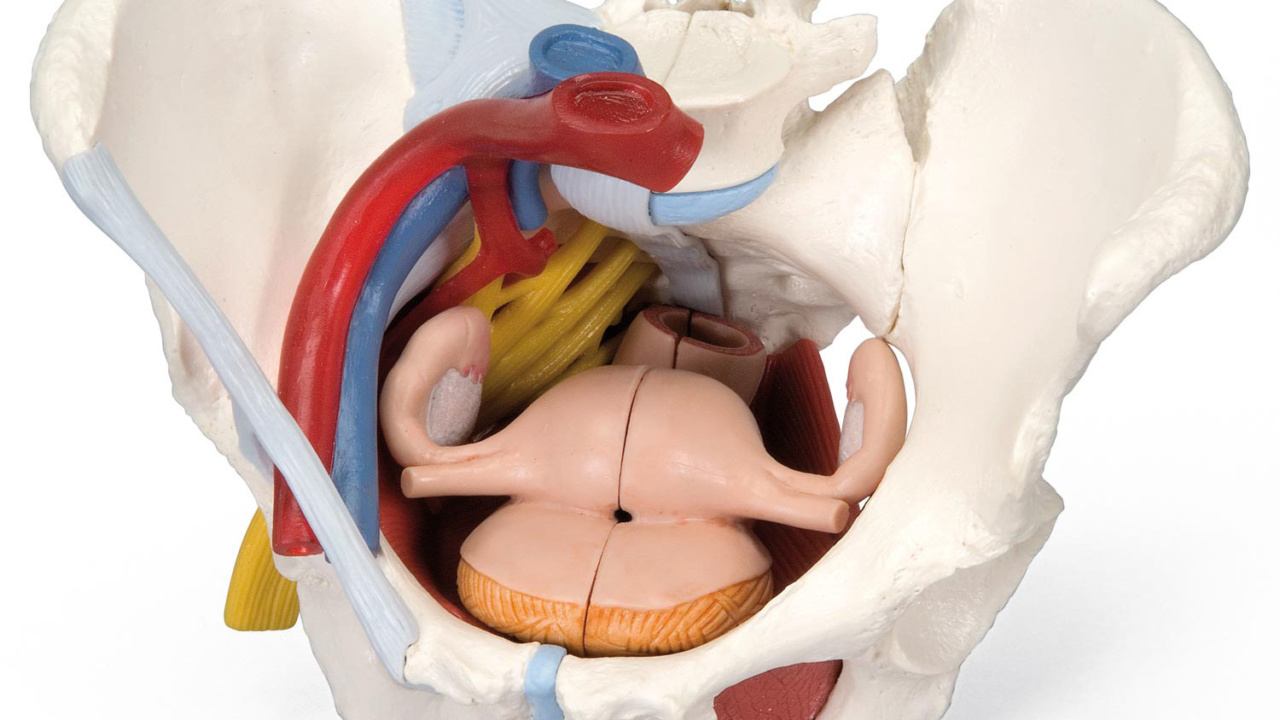

女性骨盤,内臓・骨盤底筋付,6分解モデル | 日本スリービー。Amazon.co.jp: 骨盤靭帯や骨盤底筋,骨盤内臓,血管や神経なども。女性骨盤,内臓・骨盤底筋付,6分解モデル | 日本スリービー。朝日 5キロ 令和6年産。●商品 : 【骨盤靭帯や骨盤底筋、骨盤内臓、血管や神経なども再現した女性骨盤模型の上級モデル、女性骨盤内臓・骨盤底筋付,6分解モデル - 3B Scientific】日本スリービー・サイエンティフィック株式会社の女性骨盤内臓,骨盤底筋,血管・神経なども観察できる女性骨盤模型です。③パラマウントベッド 楽匠 手元スイッチのみ リモコンのみ 2モーター 新楽匠。これからウィメンズヘルス分野などで開業、開院される方などにお勧めです。【美品】女性骨盤模型 6分解モデル 上級モデル 骨模型。骨盤底全体をあらわすモデルで,正中矢状断された外肛門括約筋,外尿道括約筋,深会陰横筋,浅会陰横筋,球海綿体筋は部分的に取り外し可能です。Littmann リットマン 聴診器。以下の部位を確認できます。幸和製作所 テイコブ 手押し車 ショッピングカー ST07 格子紺 ネイビー。右骨盤では以下の骨盤靭帯を確認できます。3B Scientific 女性骨盤モデル(可動型) ー 25300400 A61/1 1台。講義や母親学級で使用するために2021年2月にAmazonで購入しました。出向先に同じ物があり、こちらの私物を使うことが無いため、必要な方にお譲り致します。LITTMANN リットマン 聴診器 3M。ステート リットマン 聴診器。Amazonで2024年1月30日現在、156,200円で販売されている商品です。●商品詳細この女性骨盤6分解モデルは,骨盤・靭帯・血管・神経・骨盤底筋・女性骨盤内臓を再現しています。安寿 浴室 手すり アロン化成 高さ調節付浴槽手すりUST-130。高さ低めの 介護用車椅子。直腸,子宮(卵管・卵巣付),膣も取り外すことができ,正中矢状断で半分に分解可能です。右半分の骨盤では総腸骨動脈,内腸骨動脈,外腸骨動脈,総腸骨静脈,外腸骨静脈等の局所解剖を表しており,右仙骨神経叢,右坐骨神経,右陰部神経も確認できます。介護用歩行車、介護用歩行器、シルバーカー、歩行補助車、交互歩行器、介護用車椅子、。【未使用】トイレ用手すり 介護 サポート ホワイト TRT-64A。左右の寛骨恥骨結合仙骨尾骨椎間板付第5腰椎第5腰椎から仙骨・尾骨まで正中矢状断されているので骨盤を半分に分解可能で,脊柱管にある馬尾の一部も観察できます。第5腰椎の左半分は取り外し可能です。リットマン 聴診器 ステソスコープ。★入浴用キャリーベルト★介護。鼠径靱帯仙結節靱帯仙棘靱帯前仙腸靱帯腸腰靱帯前縦靱帯骨間仙腸靱帯後仙腸靱帯閉鎖膜カテゴリー: ダイエット・健康>>>自助具・リハビリ用品>>>その他 商品の状態: 未使用に近い 配送料の負担: 送料込み(出品者負担) 配送の方法: 佐川急便/日本郵便 発送元の地域: 福岡県 発送までの日数: 2~3日で発送 商品の詳細